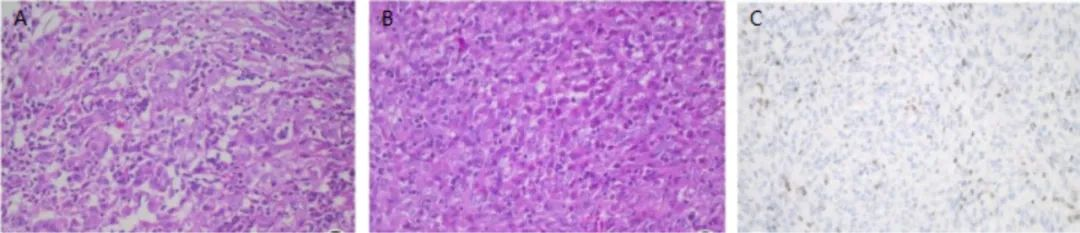

The study by Shipra Agarwal et al. first reported primary INI-1-deficient thyroid carcinoma. The pathological features of the tumor cells (as shown in Figure 1), IHC shows loss of INI-1 protein expression (a). Furthermore, this study performed INI-1 IHC staining on six other types of thyroid tumors, all showing diffuse strong positive expression (as shown in Figure 2), indicating that INI-1 immunostaining is an effective method for the differential diagnosis of INI-1-deficient thyroid carcinoma.

Figure 1. Histopathological features of INI-1-deficient thyroid carcinoma; a: Loss of INI-1 expression by IHC staining; b: Moderate amount of eosinophilic cytoplasm, small and prominent nucleoli. Focal glandular lumen formation is visible; c: Multiple intratthyroidal goiters; d-e: Perithyroidal lymphovascular emboli are visible, with hobnail-shaped cells, lymphocytes, and neutrophils infiltrating within the lesion. A few cells have eccentric nuclei resembling rhabdoid cells. f: CD31 staining confirms perithyroidal lymphovascular emboli.